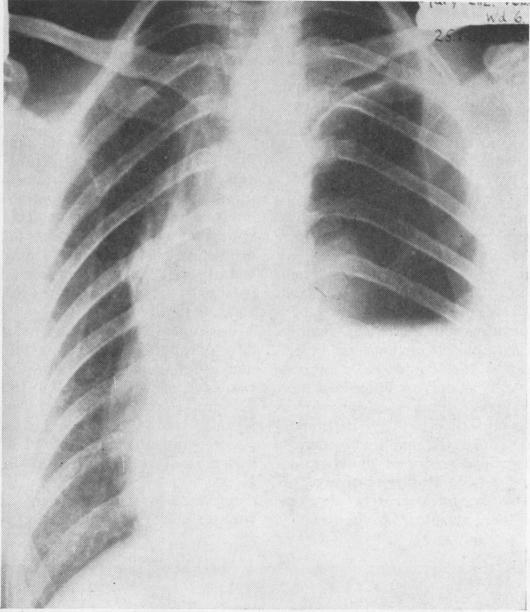

绞窄性膈疝

Strangulated diaphragmatic hernia.

Seventy-six cases of strangulated diaphragmatic hernia were reported up to 1953. An additional 64 cases reported between 1953 and 1966 are reviewed in this paper. The incidence of strangulation in various types of congenital/traumatic, hiatal, and incisional herniae is discussed. Four further cases of strangulated diaphragmatic hernia are presented. The mechanism of strangulation, its diagnosis, complications, and treatment are discussed.

截至1953年,共报告了76例绞窄性膈疝病例。本文回顾了1953年至1966年间报告的另外64例病例。讨论了各种类型的先天性/创伤性、食管裂孔和切口疝的绞窄发生率。另外还介绍了4例绞窄性膈疝病例。对绞窄的机制、诊断、并发症及治疗进行了讨论。